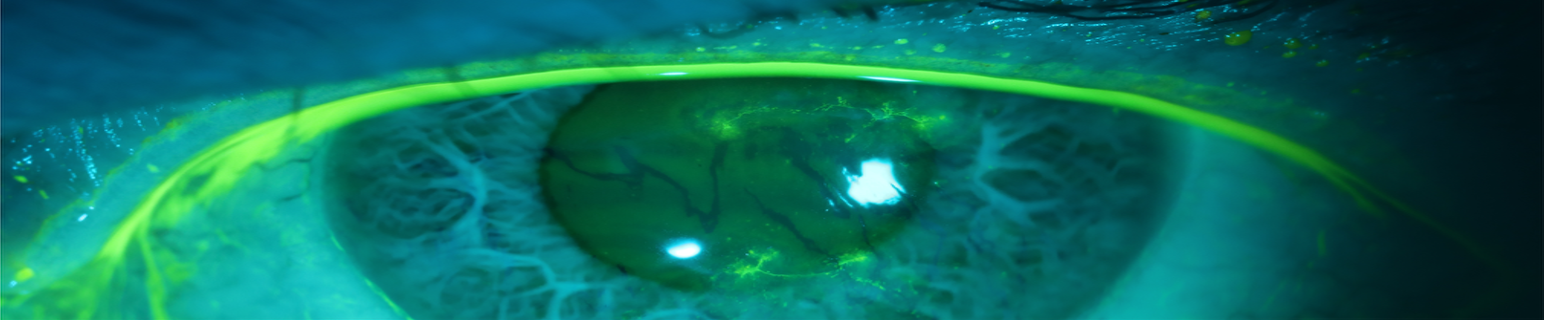

Imaging

Figure 1. Right eye with fluorescein demonstrating dendritic lesions with terminal bulbs on initial presentation.

Figure 2. Left eye with fluorescein demonstrating dendritic lesions with terminal bulbs on initial presentation.

Figure 3. Images from initial presentation illustrate branching lesions (arrow) in the epithelium with irregular borders in the left eye.

Figure 4. Photos one week after initial presentation to our clinic illustrating persistent lesions in the right eye.